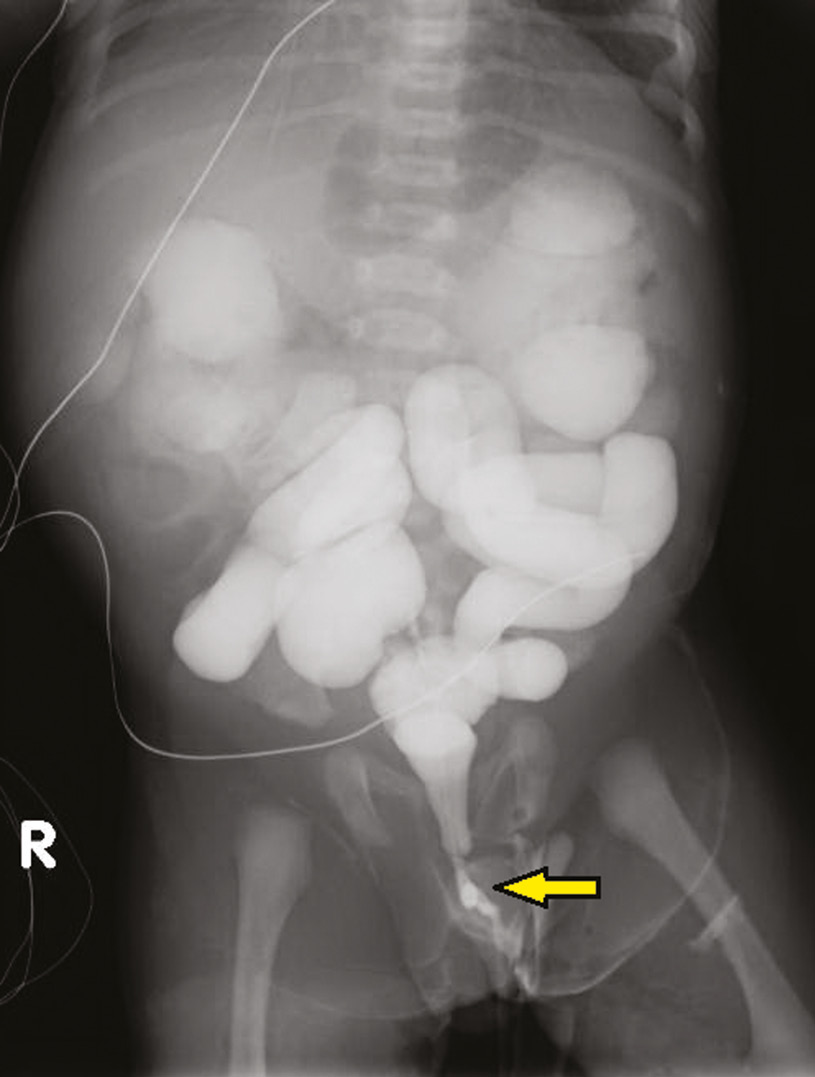

Specific Newborn and Infant Procedures (Section 3) - Essentials of Anesthesia for Infants and Neonates

Specific Newborn and Infant Procedures (Section 3) - Essentials of Anesthesia for Infants and Neonates

Specific Newborn and Infant Procedures (Section 3) - Essentials of Anesthesia for Infants and Neonates